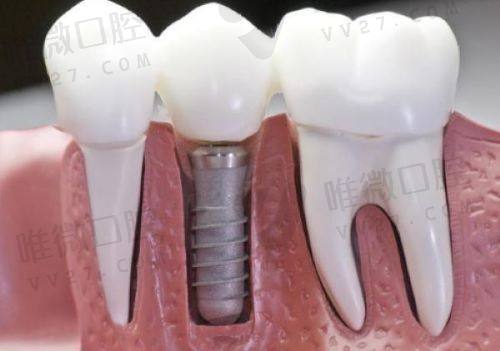

项目优势在于种植和正畸,医生技术稳定,而且价格合理:韩国登腾种植牙含冠仅从3680元起,相比市面动辄8000多的价格确实亲民不少。

价格方面也相对亲民,基础洁牙288元起,种植牙进口品牌从4800元起做活动。适合医疗保险之外想找老口碑的患者人群。

收费方面相对较高(种植牙1.2万元起),但追求高技术保护、种牙成功几率高的顾客,这里值得信赖。